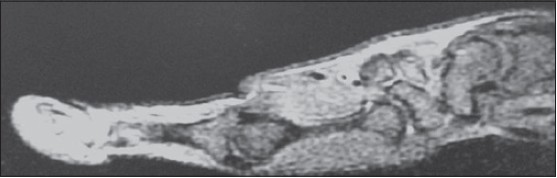

Plain X-ray of hand was normal [Figure 1]. Magnetic resonance imaging (MRI) was suggestive of swelling arising from insertion of flexure pollicis longus tendon, dark on T1 and bright MRI appearance on T2-weighted image [Figure 2] and [Figure 3]. They gave differential diagnosis of synovial swelling and glomus tumour. | Figure 2: T2 weighted Magnetic resonance imaging showing swelling arising from tendon insertion

| Figure 3: T1 weighted Magnetic resonance imaging showing swelling arising from tendon insertion

Click here to view |